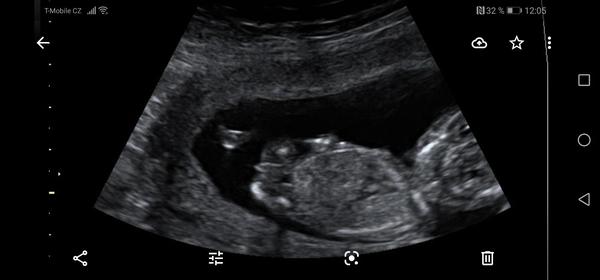

@kajda3 mám ještě tyhle. Ta jedna jsou vyloženě nožičky a bříško, je jakoby cele k nám.

@kajda3 ještě možná tuhle, tady přirození trochu je vidět, po přiblížení. Prý ty pysky jsou taky hodně velké. Prostě nevím. 😥